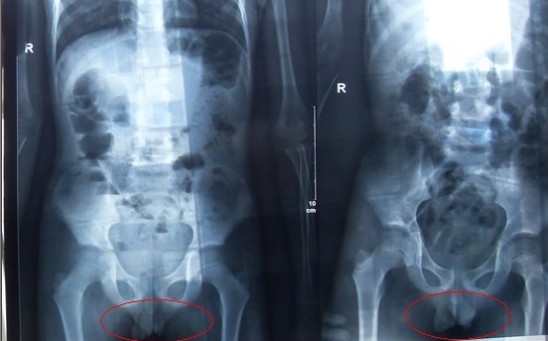

腹部立臥位X光片圖

2011年5月29日下午,陳先生的兒子安安出現嘔吐、肚子疼痛等癥狀。陳先生立即將兒子送往醫學院附院,根據醫生開出的會診單,分別對安安做了腹部立臥位2次和胸部正位1次共3次X光片檢查、診斷。醫生看X光片后排除了腸梗阻病因,判斷是闌尾炎。經過治療,不久安安身體痊愈。

可是,陳先生的一次偶然發現,讓他們一家過上了提心吊膽的日子。因為,在安安出院一個月后,陳先生偶然翻出孩子治療期間的X光片。發現在X光片中,孩子的生殖器官以及甲狀腺等敏感部位也在被放射區域中。而陳先生上網查到:人體拍攝X光片是有一定輻射的,并且輻射有可能引起基因變異等問題,他立馬陷入恐慌中。